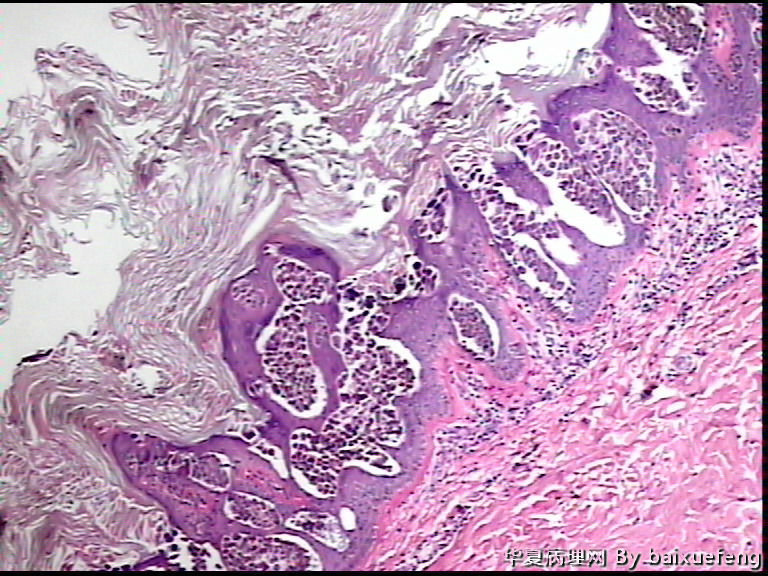

患者 女性 发现腰部皮肤肿物月余,表面0.5灰褐色结节

图1*40

图2*100

图3*100

图4*200